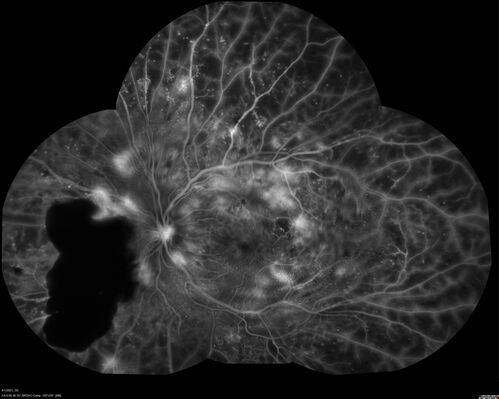

Pregnant - 25 weeks - new onset PDR and DME both eyes - Treated with PRP and ozurdex

29 year old female.  Patient is 25 weeks pregnant and having flare up of retinopathy in both eyes. She states it is worse in the left. Patient has trouble with distant vision.  At most recent visit, 1 years ago, VA was 20/20 OU.  Two years ago anterior uveitis x 1 episode with normal labs (HLAB27, FTA, ACE, Lyme).  2017-2020 – Lucentis for DME left eye only.

PMHx: Type I DM since teenager, hyperlipidemia

BP was normal